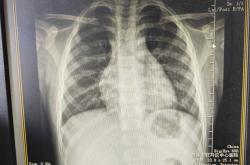

新生儿肺炎治疗费用一般在3000到15000元左右。具体得看情况哦。我家宝宝之前得轻症肺炎,住了5天院,花了大概4000多。要是病情轻,就做个胸片、血常规,用点普通抗生素,住院3 7天,费用大概...